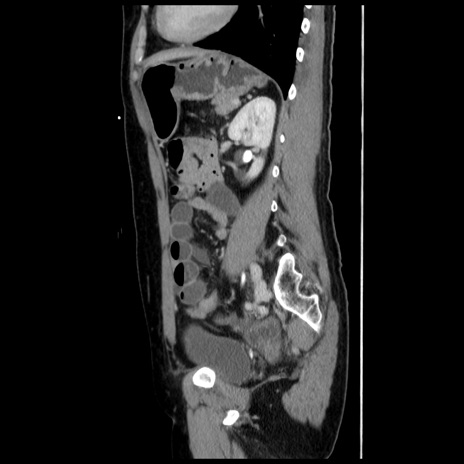

症例10(矢状断像)

【症例】 50歳代女性

【主訴】 腹痛

【現病歴】前日生レバーを食べた。今朝に排便あり。 昼前に突然発症の腹痛を生じ、当院救急外来を受診した。

【既往歴】 子宮筋腫にてで子宮全摘後

【身体所見】 意識清明、腹部:平坦、軟、下腹部やや左を中心に圧痛・反跳痛あり、筋性防御あり

【データ】WBC 7800、CRP 0.07